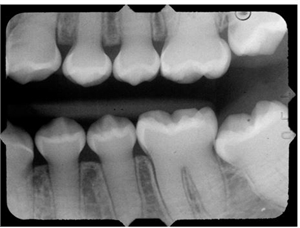

Note the shell tooth appearance with absence of pulp chambers in them.

The teth appear solid lacking pulp chambers and root canals.

They demonstrate normal enamel with extremely thin dentin and dramatically enlarged pulp chambers.